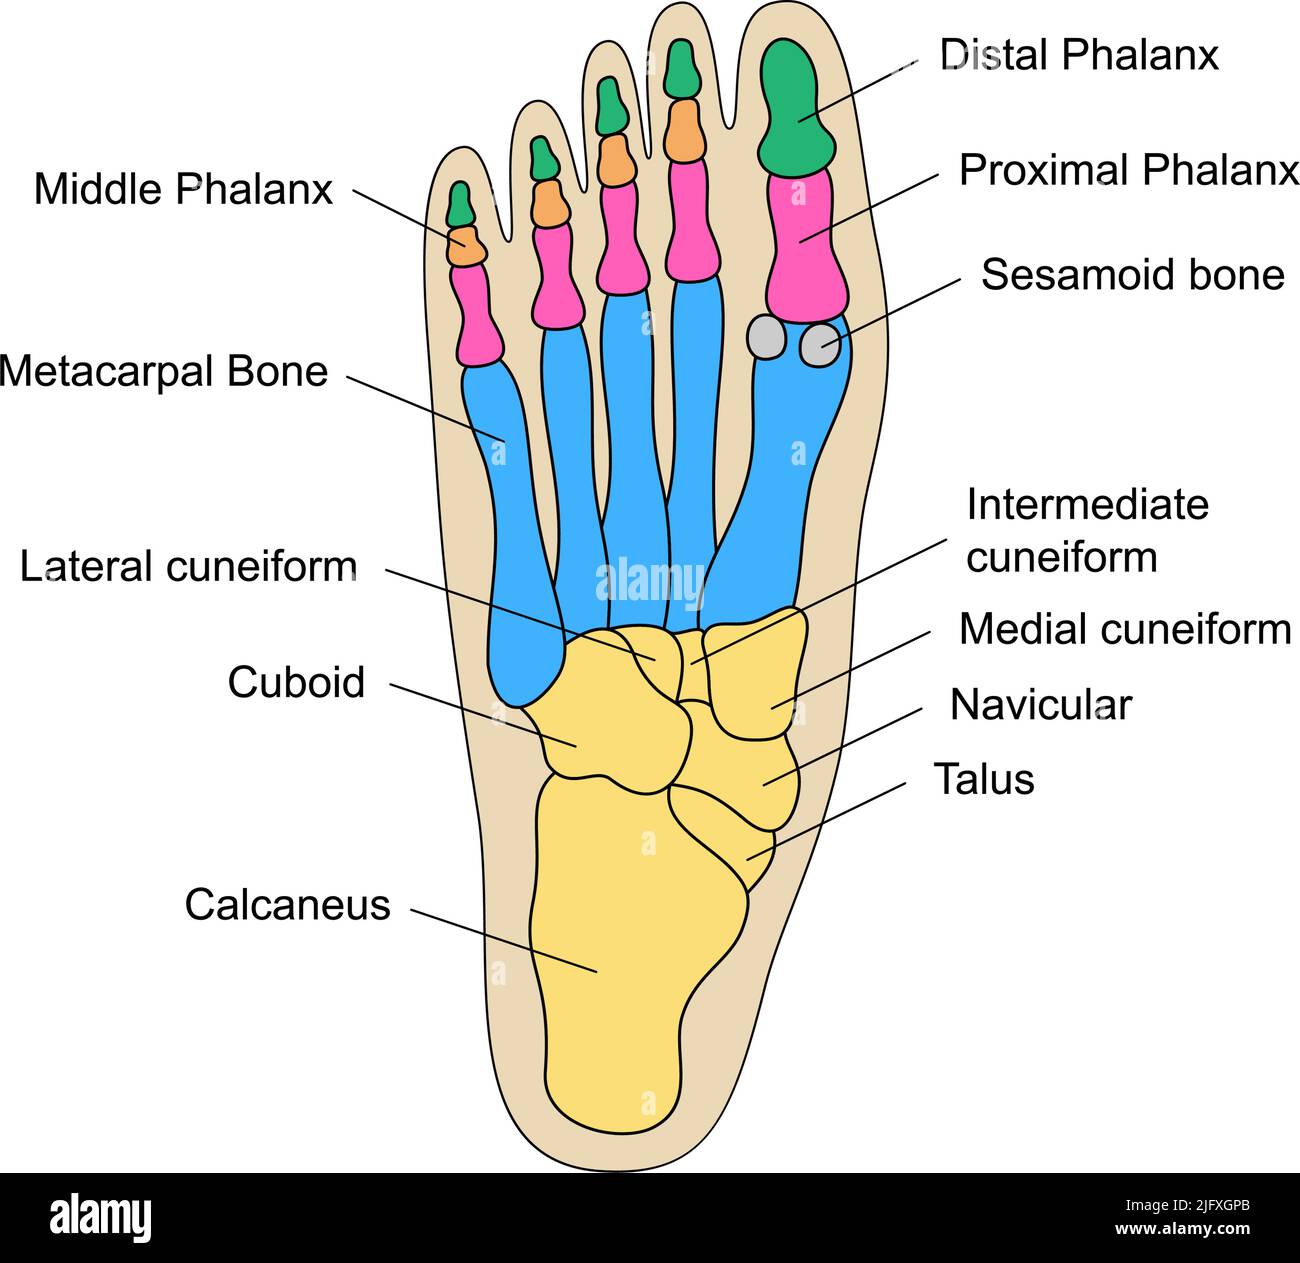

anatomia piede Bones of the human foot with the name and description of all sites

www.alamy.itBones Of The Human Foot With The Name And Description Of All Sites

www.alamy.itBones Of The Human Foot With The Name And Description Of All Sites

focusedcollection.comBones Of The Human Foot With The Name And Description Of All Sites

focusedcollection.comBones Of The Human Foot With The Name And Description Of All Sites